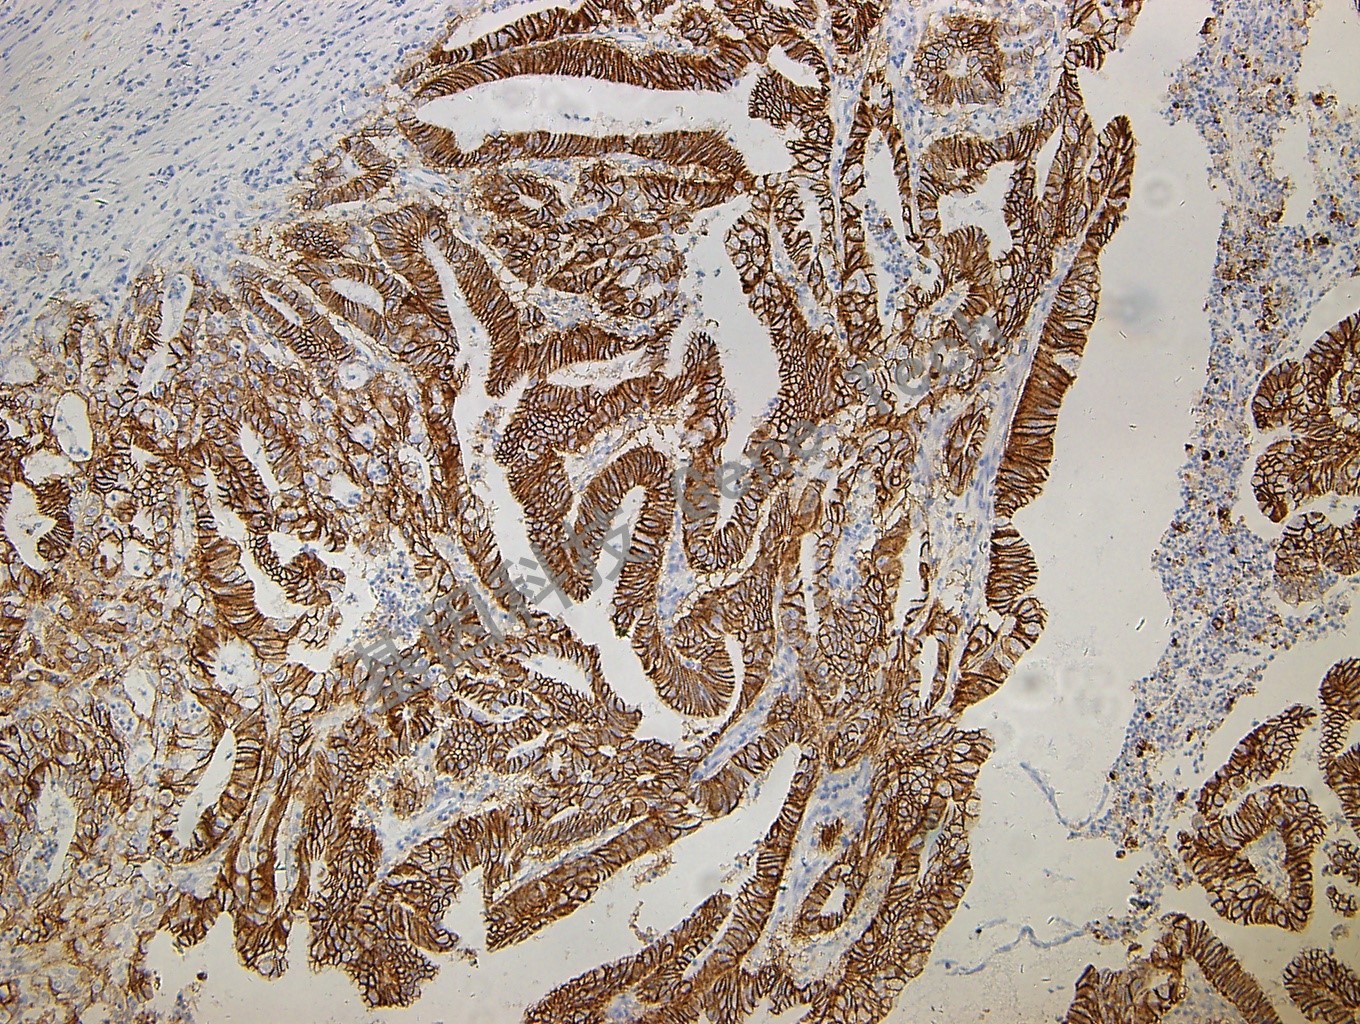

鈣黏附蛋白17(Cadherin17)抗體 鼠抗人 CDH17

| 克隆號:SDM4 | 陽性對照:結腸癌 | 陽性部位:細胞漿 |

| 簡介:肝腸- 鈣粘連蛋白(CDH17) 是在小鼠體內發現的一種表達于肝臟和小腸的新型鈣粘連蛋白,在細胞粘附、細胞識別、組織器官的發育和形態的維持等方面發揮重要作用。研究發現其在多種惡性腫瘤中有高表達,是一種與腫瘤侵襲及轉移密切相關的蛋白。目前,CDH17 可作為消化系統腺癌的診斷標記物。 | ||

| 結腸癌石蠟切片,用 Cadherin 17(GT2208)染色,細胞漿陽性,DAB 顯色。 | ||